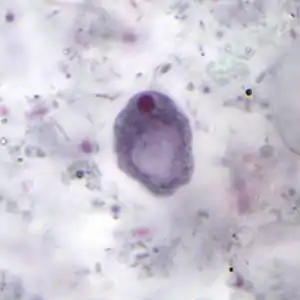

Cyst

The cysts are 8–10 micrometres in diameter, with a thick wall and a large glycogen vacuole that stains darkly with iodine. Usually harmless, it may cause amebiasis in immunologically compromised individuals. [5][6] As the second form of I. butschlii, cysts have an oval shaped- single nucleus with a prominent nuclear endosome. This form is also large, single, glycogen-filled vacuole called iodinophilous vacuole (glycogen stains with iodine). Cysts are the infective stage of I. buetschlii. Unlike trophozoites, cysts are often found in formed stools.[4]